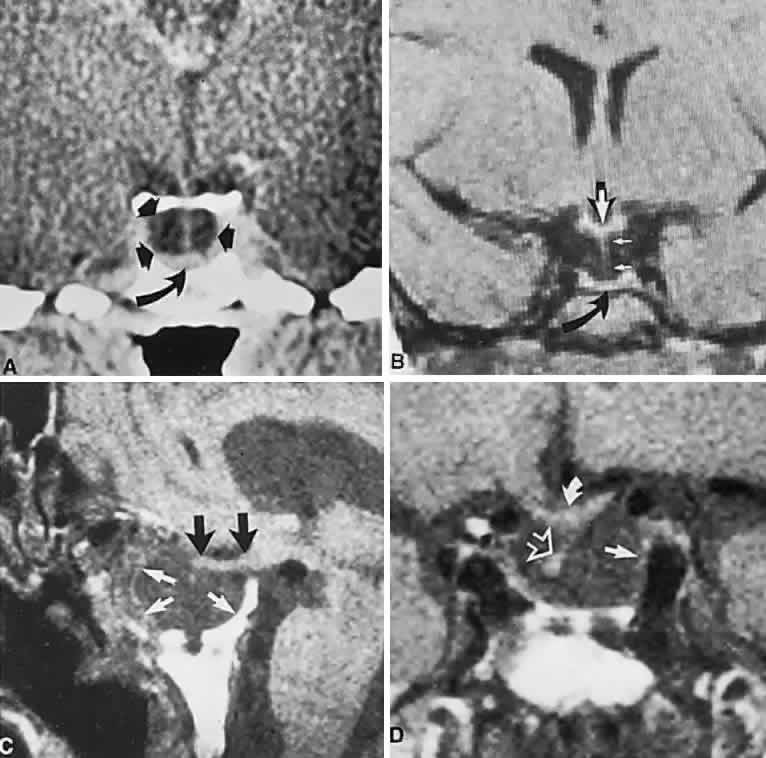

Clinical signs and symptoms include the following: acute onset of severe headache, often sickening frontal or retro-bulbar cephalgia, or other less disabling change in headache pattern; acute or rapidly progressing unilateral or bilateral (usually asymmetric) ophthalmoplegia due to rapid expansion into cavernous sinuses (see also Volume 2, Chapter 12); epistaxis or CSF rhinorrhea when the mass ruptures or erodes into the sphenoid sinus; complications of blood or necrosis debris in the CSF, with “pseudomeningitis”; rapid neurologic deterioration and obtundation, although patients need not be stuporous; and, greater or lesser degrees of hypopituitarism.62,63 Selective expansion laterally into the cavernous sinus may produce ophthalmoplegia without visual loss; selective expansion superiorly may produce visual loss without ophthalmoplegia. Almost without exception, enlargement of the sella is found even on plain skull film views; both CT and MRI detect fresh hemorrhage (Fig. 3), but MRI may fail to demonstrate acute hemorrhage unless specific sequences are employed (hemorrhage may be isointense on T1-weighted images and hypointense on T2-weighted images; in the subacute phase, extracellular methemoglobin should appear bright on both T1 and T2 sequences). Corticosteroid replacement and other supportive measures may be critical, and, in most instances, decompression through the sphenoid sinus is advisable, sooner rather than later. Bromocriptine has been suggested as a temporizing measure when signs and symptoms are modest and not progressing,64 and there are advocates65 for conservative management consisting of intravenous dexamethasone, so long as visual deficits are minimal or rapidly improve; otherwise decompressive surgery is required. Given the regularity with which pituitary apoplexy is often a delayed diagnosis, being confused with ruptured aneurysm or meningitis, for example, and that transsphenoidal surgery is a relatively simple undertaking, further procrastination in decompression of the compromised visual pathways is to be avoided.

Fig. 3. Neuroimaging of pituitary adenomas. A. Axial computed tomography (CT) section shows a round tumor mass filling the suprasellar cistern; ring enhancement (arrows) indicates subcapsular hemorrhage. B. Contrast-enhanced coronal CT section through a large invasive adenoma. Note encasement of the carotid artery (arrows) and the position of the middle cerebral artery above (arrowheads). C. Axial CT section shows lateral expansion into the cavernous sinuses (white arrows) and a necrotic cyst (black arrow). D. Subfrontal superior extent of the mass. Note the middle cerebral arteries. E. Magnetic resonance imaging of a large lobulated prolactinoma, with suprasellar extension. Note the distortion of the third ventricle (open arrows) and extension toward the temporal lobe (long arrow); the tumor has not involved the sphenoidal sinus (s). F. Chiasm (arrowheads) is draped on the superior surface of the tumor (TR, 550 milliseconds; TE, 26 milliseconds). G. Sagittal section shows suprasellar growth with the chiasm above (arrowheads); the sella (arrows) and sphenoidal sinus (s) are normal (TR, 850 milliseconds; TE, 26 milliseconds). H. Hyperintense signal (TR, 2000 milliseconds; TE, 60 milliseconds) indicates the partial cystic character. Sagittal (I) and axial (J) sections with head tilt to the right, in case of a large cystic adenoma with an interface level between newer blood (white arrow) and older blood (black arrow) (TR, 800 milliseconds; TE, 30 milliseconds). K. Signal difference is intensified (TR, 2100 milliseconds; TE, 80 milliseconds). L. Hemorrhage (bright signal, arrow) in a pituitary adenoma with headache and bitemporal field depressions. M. Without interventions, 2-month follow-up showed spontaneous involution, with normal pituitary gland (arrow), stalk, and chiasm.